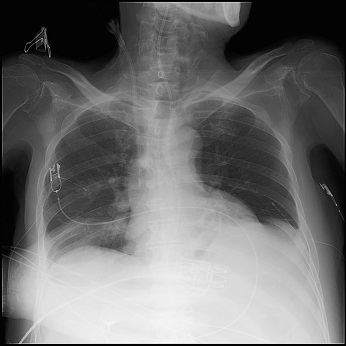

少量のエックス線用い透視を行うことで、リアルタイムでの観察が可能であり、選択的な造影検査として、各診療科がさまざまな検査を施行しています。臨床に合わせて、断層撮影(トモシンセシス)や血管造影(DSA)機能を有した装置で臨床上有用な画像を提供しています。